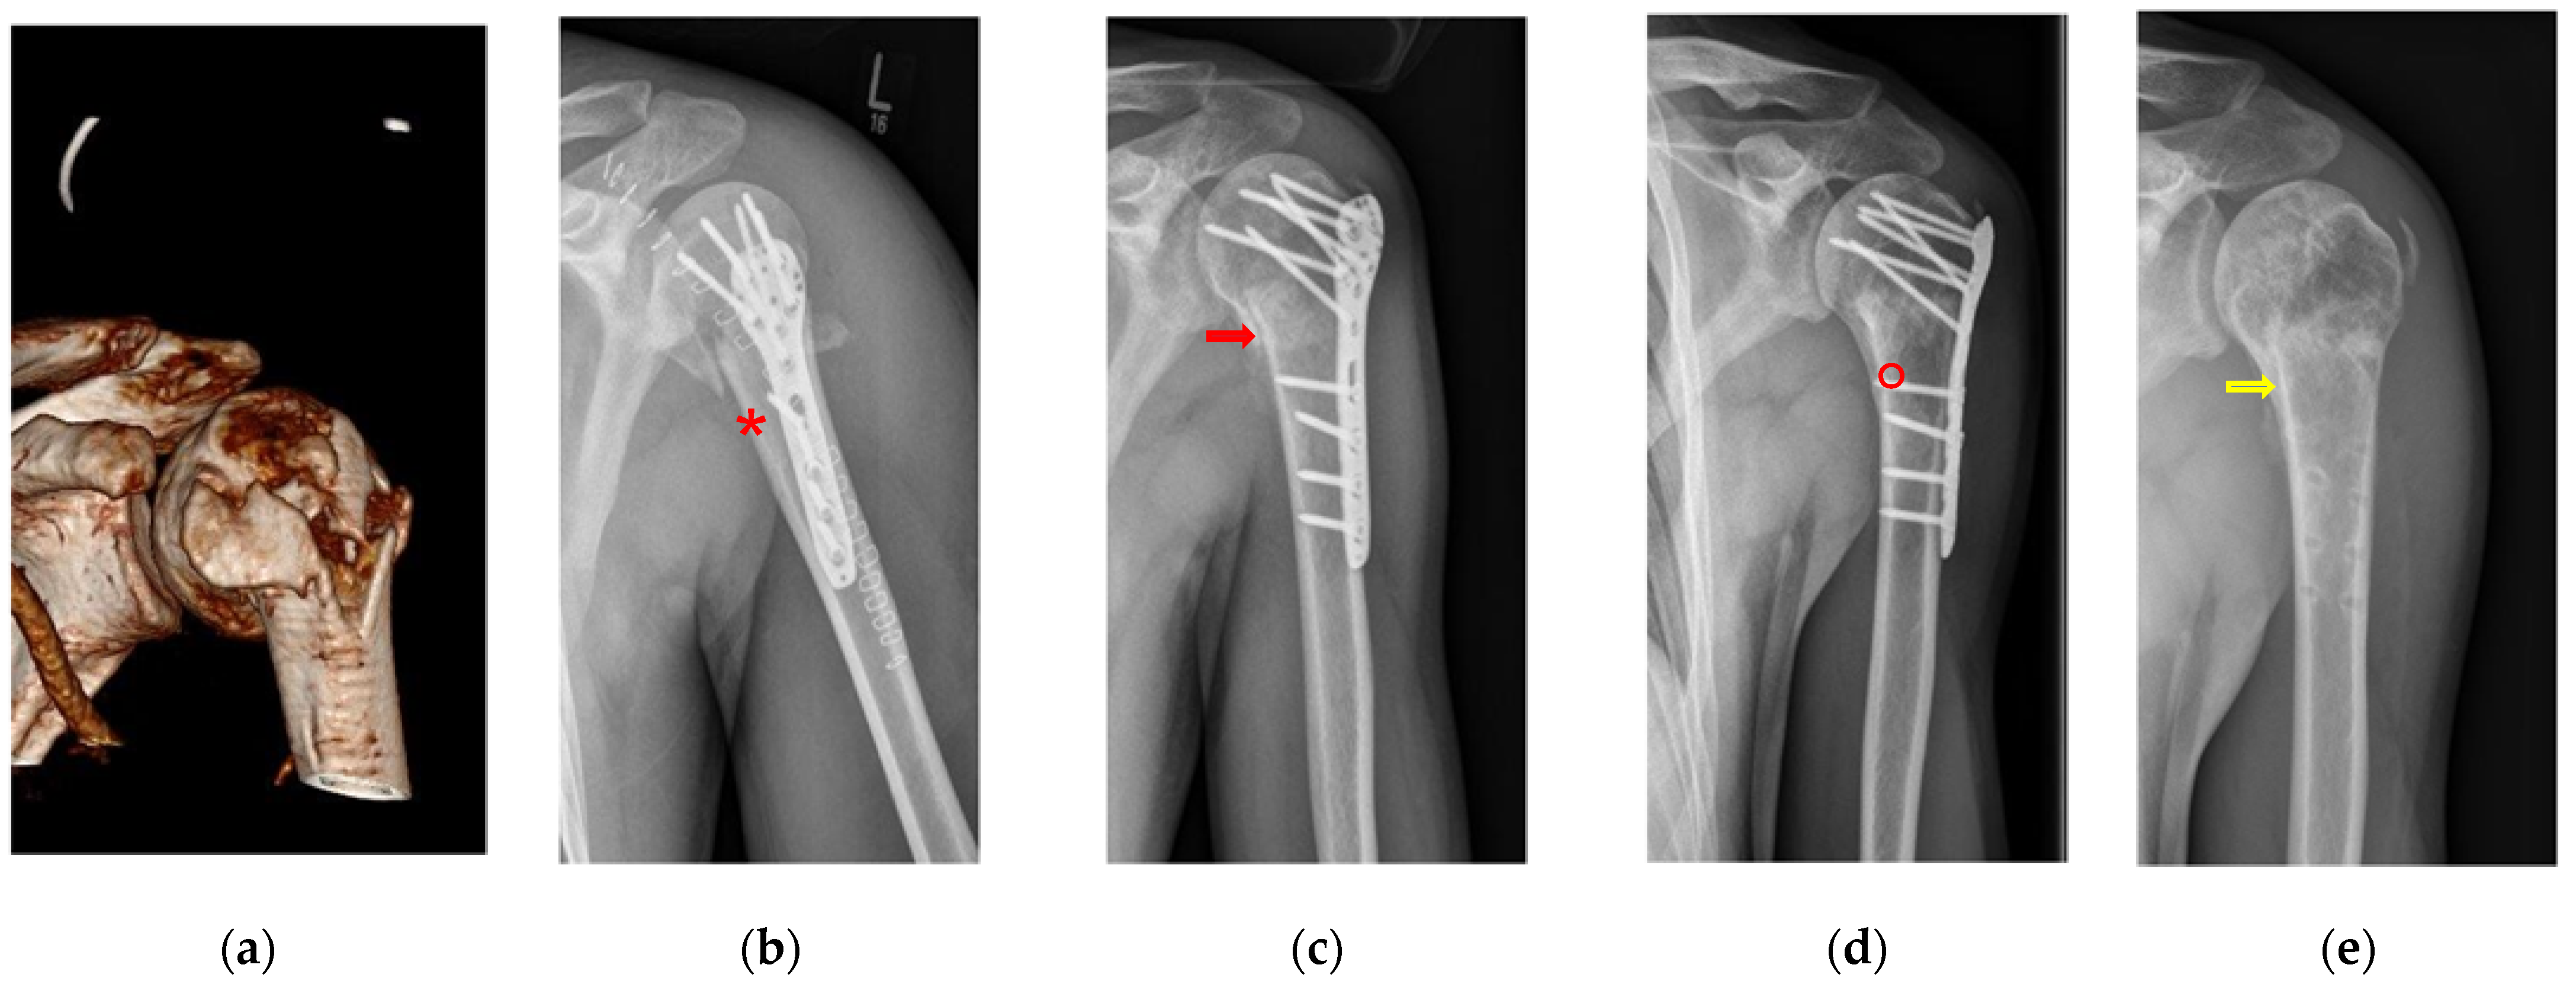

Figure 4.

Overview of pseudarthrosis post-surgery. (a) Rate of pseudarthrosis in the ED group compared with the rate of pseudarthrosis in the NHA group with significant differences. (b) An example of the clinical examination of a recent fracture treatment. (c) Conventional radiograph of a pseudarthrosis 18 years post-trauma by X-ray.

Figure 5.

Summary of selected complications demonstrating the differences between the empty defect (ED) treatment (light grey) and the calcium phosphate augmentation (CP) group (dark grey). (a) Number of all complications in the ED and the CP cohort with significant differences (p = 0.001). (b) Comparing pseudarthrosis and other complications in ED and the CP cohort demonstrated less pseudarthrosis and fewer other complications in the CP treatment cohort (p < 0.001). (c) Infection and necrosis demonstrated insignificantly fewer infections in the ED group compared to the CP treatment group.